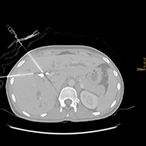

R20-Export_1_vs2 R20-Export_3_vs R20-Export_5_vs_2 R20-Export_7_vs

„Interventionelle Radiologie auf höchstem Niveau“: v.l.n.r: Biopsie einer Metastase eines Tumors der Speiseröhre durch die Wirbelsäule; Implantation einer vierfach verzweigten  Gefäßprothese in der Hauptschlagader zur Ausschaltung eines Aneurysmas; Biopsie eines Tumors in der Verzweigung des Hauptgallenganges mit zwei Biopsienadeln und die Biopsie eines Tumors in der rechten Lunge. (Bilder können durch anklicken vergrößert werden.)